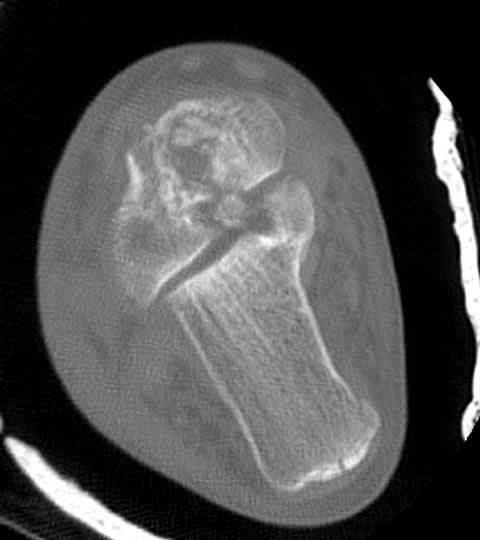

Случай с множественным оскольчатым переломом тарана оперированный из двойного доступа.

Через 2 мес.:

Через 8 мес.:

Через 14 мес.:

На ренгенограмме не уловил многоскольчатость тарана, чтобы доказать, конечно, можно было исследовать на КТ, потом КТ дает ориентацию фрагментов.

Два фрагмента суставной поверхности тарана можно восстановить боковой компрессией шурупами и дополнительно костная пластика.